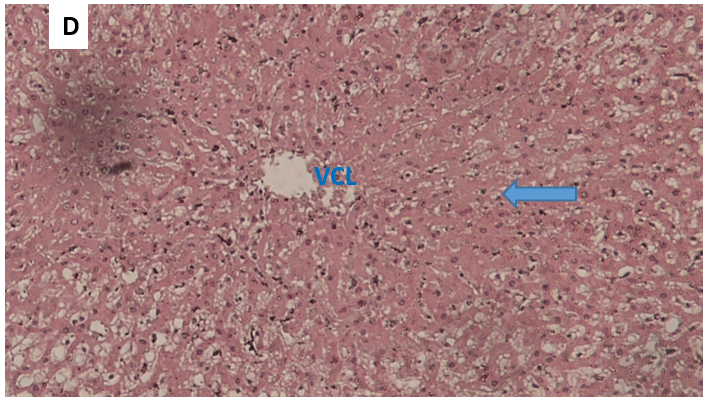

Histological images of rats from the paracetamol group

Figure 5. Microphotograph of a histological section of the liver of a rat from the paracetamol alone group, HE staining, transverse section, magnification × 100, blue arrows show tissue necrosis.

Figure 6. Microphotograph of a histological section of the liver of a rat in the paracetamol alone group, transverse section, HE staining, magnification × 400, the blue arrow indicates tissue necrosis.

Observation of microphotographs C and D: hepatocyte necrosis predominantly in the centrilobular region marked by a homogenization of the structure of the cytoplasm, a disappearance of the nuclei and cell boundaries. At a distance from the centrilobular vein, the structure of the hepatocytes remains relatively preserved.